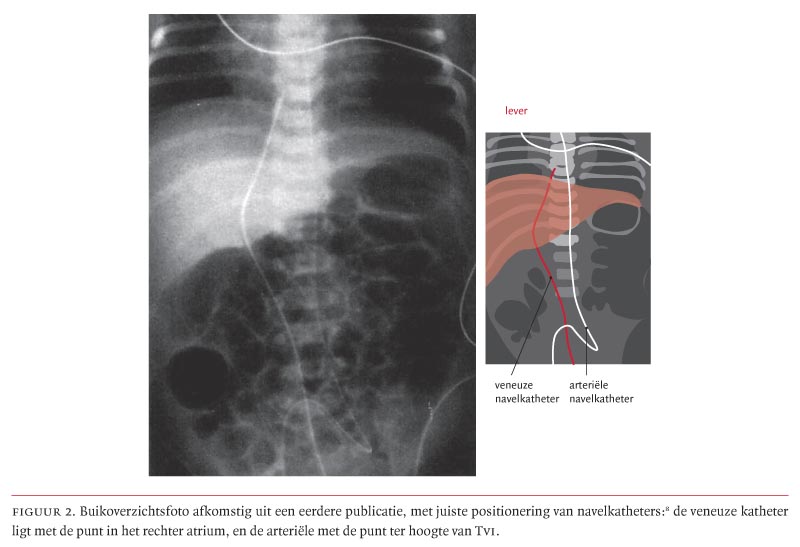

De veneuze navelkatheter volgt de V. umbilicalis in de richting van de ductus venosus die in de lever gelegen is.8 Hierna vervolgt de veneuze katheter zijn weg naar de V. cava inferior om juist vóór het rechter atrium te eindigen. Dientengevolge is op een buikoverzichtsfoto een juist gepositioneerde veneuze katheter rechts naast de wervelkolom ter hoogte van het diafragma gelegen (figuur 2).8

Een arteriële navelkatheter wordt via een van beide Aa. umbilicales en vervolgens via de Aa. iliacae internae in de aorta ingebracht. Een arteriële katheter dient op een buikoverzichtsfoto juist links of ter plaatse van de wervelkolom gepositioneerd te zijn. De tip behoort tussen de 4e en de 9e thoracale wervel of ter hoogte van de 4e lumbale wervel te liggen (zie figuur 2).8

Wij danken collega’s Beek en Termote voor hun reactie. De betreffende figuur 2, afkomstig uit een eerdere publicatie, is uitsluitend bedoeld om het verschil te illustreren tussen de loop en de ligging van respectievelijk een veneuze en een arteriële navelkatheter. De tip van de veneuze lijn ligt, zoals beschreven in het onderschrift van figuur 2, in het rechter atrium. In de praktijk zou de lijn teruggetrokken moeten worden tot in de V. cava inferior, alvorens deze te gebruiken. Dit is inderdaad niet duidelijk genoeg aangegeven in het onderschrift van figuur 2. In de tekst van ons artikel wordt de juiste ligging van een veneuze navelkatheter beschreven: de tip dient in de V. cava inferior te liggen, juist onder het rechter atrium. Het commentaar van Beek en Termote onderschrijft nog eens extra hoe een juiste positie van een veneuze en arteriële navelkatheter aan de hand van anatomische structuren röntgenologisch dient te worden gecontroleerd. Het spreekt voor zich dat hiervoor een volledige thorax-buikoverzichtsfoto (dit is een foto inclusief het kleine bekken) dient te worden gemaakt. Naast de punten die zijn genoemd in onze tekst, kan het maken van een laterale buikoverzichtsfoto toegevoegde waarde hebben voor het onderscheiden van een veneuze dan wel arteriële ligging van een navelkatheter.